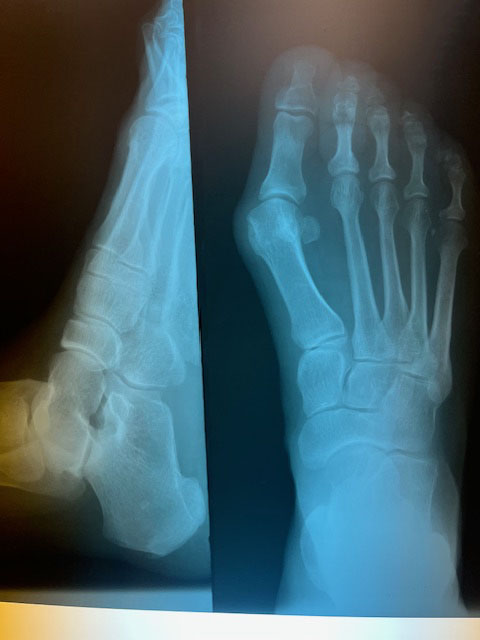

This testimonial is regarding Dr. Sean Stoddard and the work he performed on my ankle in July of 2012. Prior to being referred to Dr. Stoddard, I was in constant pain as the result of an ankle injury that had occurred during a motorcycle accident in 1993. Visits to orthopedic surgeons had resulted only in recommedations for an ankle fusion, a procedure that I was told by former recipients may not be successful at stopping the pain. The pain in my ankle had become unbearable during the last couple years leading up to my first consultation with Dr Stoddard. I was walking with a cane and taking pain medication, which was affecting my quality of life. A third party mentioned Dr Stoddard and his Foot and Ankle Clinic. My consultation with him revealed that I was a candidate for a total ankle or Inbone® ankle replacement. The promise of pain relief without a fusion seemed almost too good to be true. Surgery was scheduled and performed. After several months of rehab I was walking and without pain. Today my quality of life has vastly improved and I will always be grateful to Dr. Stoddard.

In March 2011 I contracted Necrotizing Fasciitis in my lower left leg/ankle/foot. The infection resulted in the loss of nearly 40% of my ankle bone and limited my range of movement to less than 10% – up/down, no lateral movement what so ever. Also my foot and ankle were in constant pain. I was on a daily regimen of 75mg Tramadol 2x’s daily until the ankle was replaced in January 2014 by Dr. Stoddard.

In December 2013 I consulted with Dr. Stoddard on my ankle and what reconstruction could be performed to increase range of movement and reduce or eliminate the constant and nagging pain. (The pain level in my ankle was a constant – numbing – 8-9 on a scale of 1-10, 24/7.

Dr. Stoddard evaluated my ankle, my desire to increase mobility and reduce the chronic pain. After several consults with other Orthopedics to discuss my ankle and its ‘current’ condition – Frozen bone mass, Dr. Stoddard recommended a total ankle replacement.